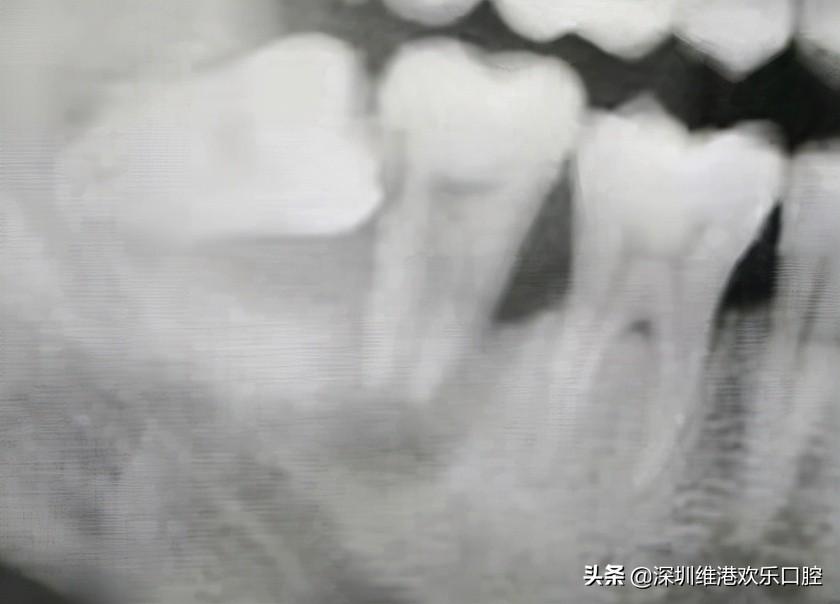

一位患者,智齒長歪頂壞了鄰牙,導(dǎo)致鄰牙鬆動(dòng),極其容易脫落,患者自己也一度以為可能保不住了。但是高主任在仔細(xì)檢查了患者的實(shí)際情況,認(rèn)為還有保留住的可能。所以高利民主任先把這個(gè)極松的7號牙和6號牙用玻璃離子粘結(jié)穩(wěn),先將7牙磨低磨小開髓置Fc棉暫封,然后拔掉智齒,等7牙慢慢恢復(fù)。經(jīng)過幾個(gè)月后,患者的原始牙得到了很好的恢復(fù)保留。